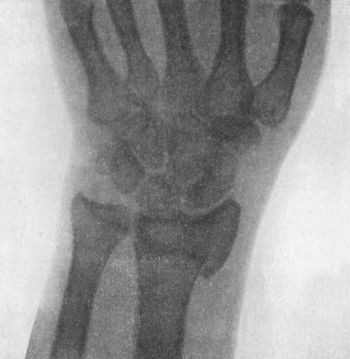

109 49.Radiogram showing Fracture of Navicular (Scaphoid) Bone

111 50.Dorsal Dislocation of Wrist at Radio-carpal Articulation